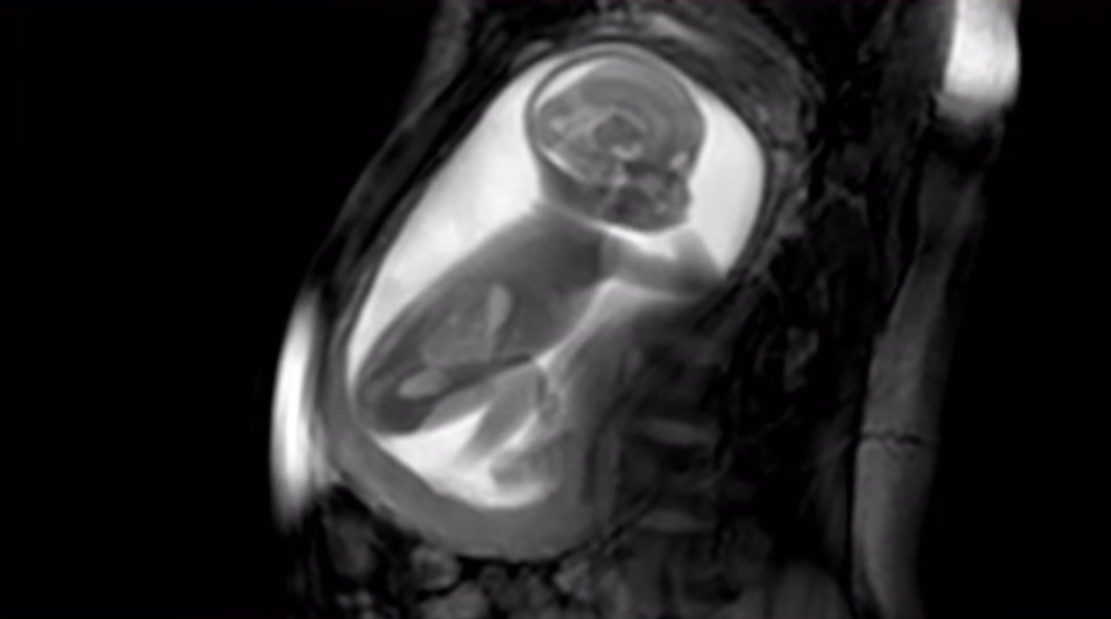

El material que consiguen es tan detallado que se puede ver al bebé girando el cuello, jugando con el cordón, saltando, encongiéndose, etc. En el caso del vídeo, el feto tiene 20 semanas de vida y por eso se le ve el cuerpo entero.

Y esto es lo más increíble: mediante unos algoritmos, el ecógrafo es capaz de captar la imagen de todo el útero e incluso el cuerpo de la madre, en alta calidad. Nada de ver un brazo, ahora una pierna, ahora la cabeza, ahora "no sé qué es esto", etc. En una sola imagen se ve al bebé por completo, de manera que se puede tener una idea muy clara de lo que está haciendo en cada momento.

Gracias al método de captación de imágenes, no sólo puede verse el exterior del bebé, sino también el interior, con gran definición. De este modo, incluso los bebés que se mueven mucho en el útero pueden ser grabados para analizar después las imágenes con detenimiento, y valorar si todo se está desarrollando con normalidad.

Se pueden ver las estructuras internas del cuerpo, independientemente de si hay hueso, músculo o grasa en el camino; y en algunos casos puede darnos incluso imágenes más detalladas que una ecografía. Es importante destacar que también es una de las pocas técnicas de imagen que son seguras durante el embarazo.

Como acabo de explicar, lo novedoso del sistema no es solo la definición y la capacidad de abarcar un gran campo de visión, sino también la de poder obtener, de manera estable, imágenes de bebés que se mueven más de lo deseable para verlos con detenimiento.

Son muchas las ecografías en que el bebé está tan inquieto que apenas se deja ver, mientras que con este sistema se pueden obtener resultados estables y válidos, muy útiles para hacer posibles diagnósticos antes y, en consecuencia, poder actuar también antes, si hiciera falta algún tipo de intervención médica.